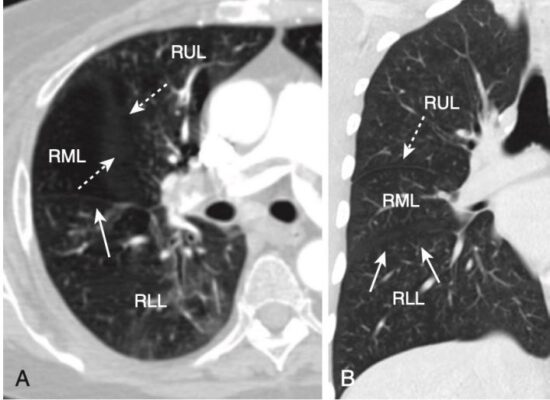

- Tùy thuộc vào độ dày của lát cắt, các rãnh sẽ có thể nhìn thấy dưới dạng các đường trắng mỏng hoặc bằng một dải vô mạch dày khoảng 2 cm khi chúng đi chéo qua phổi (Hình 16).

- Rãnh nhỏ đi cùng mặt phẳng ngang như với hình ảnh CT cắt ngang nên thường không thể nhìn thấy, ngoại trừ ở mặt phẳng đứng dọc hoặc mặt phẳng trán. Tuy nhiên, giống như các rãnh lớn, có thể suy luận ra vị trí của rãnh nhỏ bởi một vùng vô mạch giữa các thùy trên và thùy giữa phải (xem Hình 16, A).

- Rãnh lớn phân cách thuỳ trên với thuỳ thấp hơn. Ở bên phải, rãnh bé phân chia thùy giữa. Tương tự của nó ở bên trái là phân thuỳ lưỡi của thùy trên trái (Hình 17).